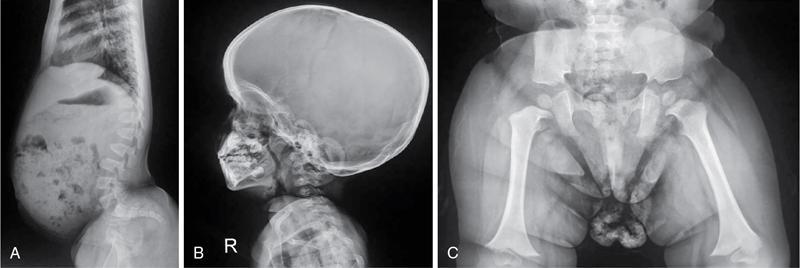

MISCELLANEOUS PAEDIATRIC RADIOGRAPHY – TECHNIQUES AND INTERPRETATION: SKELETAL SURVEY Padma V. Badhe The skeletal survey, generally performed in children, is a set of radiographs done in order to evaluate the entire skeleton. A skeletal survey, commonly used to evaluate skeletal dysplasias, acquired metabolic disorders and suspected child abuse, is still the key radiological investigation for the same. Hence, an explicit understanding of the technique along with the common disorders forms the basis of making a diagnosis in these paediatric pathologies. A skeletal survey is done for various skeletal dysplasias, non-accidental injury (battered baby syndrome) and suspected child abuse. It can also be done in cases of metabolic bone diseases, disseminated infections, multiple myeloma, eosinophilic granuloma. It is also used in evaluation of metastatic bone diseases and polyarticular arthropathy. Orthogonal views of the skull, spine, pelvis and one extremity are taken, preferable in standing position. For preterm babies/newborns, AP and lateral views of babygram may be taken. Projections: For skeletal dysplasias: Additional views: Both extremities may be taken if epiphyseal abnormalities and limb asymmetry is present. Focused views for specific pathologies may be taken. When a diagnosis remains uncertain, 1 year follow up is usually recommended. For preterm babies/newborns: AP and lateral views of babygram may be taken with additional specific views for extremities. For suspected non-accidental injury (NAI): AP and oblique view of chest is taken for better evaluation of the ribs. AP view of abdomen with pelvis. Both upper and lower limbs are evaluated. In lower limbs, two projections in AP and lateral (one with both femur including hip and knee joints; and another for foot and ankle) is taken. AP and lateral views of whole spine, skull. Oblique view of hands. A babygram should be avoided in cases of NAI, as subtle fractures are easily missed. Proper legal documentation while taking the views is very important and ideally two health care professionals must be present. For metabolic disorders: entire skeletal survey is usually not required. Specific views of hands, knees and spine may be taken with additional views depending on the suspected pathology. Centring point: Varies according to the part being examined. Angulation, collimation and orientation: Varies according to the part being examined. Images must be well collimated to obtain lower radiation dose. Detector size: Varies according to the part being examined: 8″ × 10″, 10″ × 12″, 11″ × 14″. Exposure: Ideally high kVp images are taken to reduce radiation dose. But in suspected NAI, low kVp/high mA images are recommended to better demonstrate findings. SID (Source Image Distance):100 cm Grid: Grids are not routinely used to image spine, pelvis, skull and abdomen in children. Radiation dosage: 0.3–3 mSv Essential image characteristics: Adequate spatial resolution, high signal to noise ratio, low kVp (50–70) for high contrast should be done. Excellent bone and soft tissue details are required. The presentation of skeletal dysplasia can range anywhere from minimal stunting of growth and bowing of limbs to severe dwarfism and multiple fractures. Knowledge of the commonly encountered dysplasias with an approach to arrive at a diagnosis is vital in any Radiologist’s practice The following flow chart summarizes the classification of important skeletal dysplasia: The following table summarizes the various dysplasias affecting the axial skeleton: TABLE 7.5.1.1 The following flow chart summarizes the working approach to skeletal dysplasias: Osteopetrosis (Albers-Schonberg disease/Marble bone disease) (Fig 7.5.1.1): Osteopetrosis clinically presents with anaemia/thrombocytopenia or cranial nerve compression. Radiological features include generalized increase in bone density with loss of medullary space. However, cortico-medullary appreciation with cortical thinning is also rarely seen. Bone within bone appearance with Erlenmeyer flask deformity is also noted. Pyknodysostosis (Figs. 7.5.1.2 and 7.5.1.3): patient presents with short stature. Unlike osteopetrosis, there is no anaemia. Radiographs show generalized increase in bone density with preserved medullary canal. There is mandibular hypoplasia with obtuse angle. Acro-osteolysis is also a feature. Dental caries with osteomyelitis of the jaw may be seen. Sclerosing dysplasia presenting as wavy undulating new bone formation. Usually monomelic, lower limb and along one side. The classic appearance is described as Dripping candle Wax sign. It is a Sclerosing dysplasia with radiological features of symmetric juxta-articular involvement in epimetaphyseal region. They are 1–10 mm in diameter and uniform in size. No metabolic activity is seen on bone scans. This skeletal dysplasia shows diffuse decrease in bone density with paper-thin cortex. Fractures heal in normal time but shows callus with poorly cellular matrix. Wormian bones and enlarged sinuses may be seen. Codfish vertebra (Biconcave vertebra) may be seen. Metaphyseal corner fractures are not seen in osteogenesis imperfecta that helps to differentiate it from battered baby syndrome. There are four types of OI out of which type one is most common (Figs. 7.5.1.6 and 7.5.1.7). The radiological features of MPS include Osteopenia and Universal platyspondyly. The intervertebral disc spaces are maintained. Proximal pointed metacarpals is an important radiological finding. Hurler’s syndrome show anteroinferior beaking with short and wide metacarpals. Varus deformity of humerus is characteristically seen in Hurler’s syndrome (Fig. 7.5.1.8). Mental retardation & corneal clouding is seen in Hurler’s syndrome whereas these Hunter’s disease has normal intelligence with no corneal clouding. Morquio’s syndrome shows central beaking (Fig 7.5.1.9). This skeletal dysplasia shows normal bone density with rhizomelic limb shortening and normal trunk. Narrowing of spinal canal is classically seen with decrease in the Interpedicular distance caudally. Other radiological features include trident hand (separation of middle & third fingers), Champagne glass pelvis (short, flat ilia and small sciatic notch), bullet nose vertebra and overexpansion of skull with narrow foramen magnum (Fig. 7.5.1.10). This skeletal dysplasia is characterized by normal bone density with dwarfism and normal craniofacial skeleton. The interpedicular distance is normal. There is severe platyspondyly with anterior tonguing (disappears at older age). Other radiological features include increased disc space, short stubby metacarpals, small irregular epiphysis and widened metaphysis. Anterior tonguing is a feature of Pseudoachondroplasia. This form of skeletal dysplasia involves the spine and epiphyses (Fig. 7.5.1.11). There is normal bone density with rhizomelia. Spine and Pelvis can be involved. Premature osteoarthritis can be seen. The other characteristic features include Platyspondyly and small irregular epiphysis. There are two forms Spondyloepiphyseal dysplasia Congenital and Spondyloepiphyseal dysplasia Tarda. Spondyloepiphyseal dysplasia Congenita is Autosomal dominant and shows pear-shaped vertebrae. Spondyloepiphyseal dysplasia Tarda is X Linked recessive with heaped up vertebrae. It has two forms. The first form is Conradi Hunermann syndrome which is autosomal dominant characterized by asymmetric limb shortening with metaphyseal flaring (Fig. 7.5.1.12). The Autosomal recessive form is Fatal in first few years. Rickets: Rickets refers to deficient mineralization of the growth plate in the paediatric population due to deficiency of vitamin D. In an immature skeleton, there is abnormal mineralization at the zone of provisional calcification in the metaphysis due to osteoid deposition resulting in widening of the growth plate. The features of rickets include fraying, splaying and cupping (Fig. 7.5.1.13). Fraying denotes indistinct margins of the metaphysis whereas splaying denotes widening of metaphyseal ends. Term ‘Cupping’ is used for increased concavity of the metaphysis. These findings are typically seen involving areas of active growth (e.g. distal femur and proximal tibia in the knee) Bowing is a result of associated osteomalacia leading to weakening of weight-bearing lower limb bones. Other bone deformities such as genu valga, genu varum, protrusio acetabuli can also be seen. The lower ribs may also be drawn inwards inferiorly by the attachment of the diaphragm this is called Harrison’s sulcus. Scurvy: Scurvy is a result of dietary deficiency of Vitamin C (ascorbic acid). The classic presentation is that of a patient with an increased bleeding tendency and osteopenia with poor wound healing. Features of scurvy include generalized osteopenia with cortical thinning termed as ‘pencil-point’ cortex. Other radiological findings include the periosteal reaction due to subperiosteal haemorrhage. Expansion of the costochondral junctions occurs forming scorbutic rosary. Bleeding into the joint spaces may result in hemarthrosis. Circular, opaque radiologic shadow surrounding epiphyseal centres of ossification may result from bleeding (Wimberger ring sign) (Fig. 7.5.1.14). Frankel line may be seen. It represents dense zone of provisional calcification. Lucent metaphyseal band is seen underlying Frankel line called as Trümmerfeld zone. Metaphyseal spurs may be seen that result in cupping of the metaphysis (Pelkin spur). Pelkin fracture (metaphyseal corner fracture) can also be seen. Images obtained must be of good resolution with adequate bone and soft tissue details. Additional views: They have already been described in positioning. CT Brain in can be done in cases of NAI to look for subdural hematomas. A skeletal survey is the first-line imaging modality for evaluation of skeletal dysplasia, nonaccidental injury and metabolic bone diseases. The skeletal survey must be tailored according to the respective indication. It helps to characterize syndromic patterns in skeletal dysplasias, with evaluation of complications. In cases of diagnostic dilemmas, additional focused view and occasionally yearly follow-up is recommended. A high index of suspicion is needed in utilizing skeletal survey as a diagnostic modality in NAI. At the same time, one must also remember the legal and social implications of making this diagnosis. BABYGRAM Babygram is a colloquial term used for a radiograph of the whole body of a newborn or just the chest and abdomen (thoracoabdominal babygram) on a single image. As the name suggests it is a rather non-targeted study. It is most commonly requested after line placement. Evaluation of skeletal abnormalities in a deceased foetus is typically performed using anteroposterior and lateral views of a babygram. It helps in pointing out skeletal causes of death in stillborn or dead foetuses. This will help the treating physician and parents understand the reason for baby’s death. This will also help in future genetic counselling of the couple. Sometimes chest or abdominal radiographs of the baby are requested but due to radiographers error or inexperience with small babies, there is inclusion of the region not to be assessed leading to a false babygram. Babygram is most frequently done after line placement in neonates, to view the position of the umbilical vein or artery catheter and to confirm appropriate placement. It is a useful modality in skeletal dysplasias (Fig. 7.5.1.15) like osteogenesis imperfecta, thanatophoric dysplasia and chondrodysplasia punctata. It can also be used for skeletal deformations probably caused by foetus akinesia and in cases of Caudal regression syndrome. In stillborn foetuses, it is used for evaluation of skeletal dysplasias prior to an autopsy (Fig. 7.5.1.16). It is also used in screening for surfactant deficiency and in cases of Necrotizing Enterocolitis in preterm babies where it can help to see the bowel dilatation, intramural and portal venous gas. It can be done in aneuploidies like trisomy 18 and in cases of sudden infantile death syndrome. All the essential equipment and room need to be prepared including the exposure factor. This should be done prior to placing the baby on the table to prevent any neonatal heat loss. Ensure that the baby is correctly identified. Give brief explanation to the patient’s parents regarding the procedure, its risks and benefits. Ensure that the accompanying relative is not pregnant (if female). Parents/guardians/nurses should be instructed to hold the baby with arms above the head and legs straight down. Sandbags/tapes can be used to immobilize the baby. Avoid taking the radiograph when baby is crying. Normal appearance: The endotracheal tube should lie in the lower third of trachea, distance can vary with position of baby’s head. Umbilical artery catheter has an inferior dip along the internal iliac artery, which then turns superiorly along the aorta. The tip should lie in the mid-thoracic aorta (T6–T10) or lower (L3–L4) away from aortic branches to prevent any thrombosis. Umbilical venous catheter does not have the inferior curvature, but rather a posterolateral angulation to the right near the liver through the ductus venosus. The tip should lie in the superior IVC or right atrium at T8/T9 vertebral level (Fig. 7.5.1.17). Portal venous gas may be seen initially after insertion. In a stillborn foetus, the approximate gestation age of the foetus and corresponding ossification centres must be known. In early gestation, the lack of appearance of an ossification centre may be mistaken for skeletal dysplasia. Both chest and abdomen should be included. In a rotated patient, the distance between the spinous process to medial end of clavicles will be asymmetric. The medial end of clavicle should overlap the lung apex, if above, suggests lordotic image. Motion artefacts to be reduced as much as possible. A crying neonate may result in an expiratory film, and hence must be evaluated accordingly. In evaluation of skeletal dysplasias in the newborn, additional views of skull and hand have to be obtained. Baby gram is a useful diagnostic investigation for position of the paediatric umbilical catheters. It helps in general survey in skeletal dysplasia (Fig. 7.5.1.18). It is a simple, effective study in deceased foetus for diagnosis and further counselling, sometimes obviating the need for an autopsy. As baby gram is a non-targeted study, it increases the dose of radiation for the baby. As the exposure settings remain same for the entire body of the baby, the quality of the image decreases. This increases the chances of missing subtle findings. The babygram in a neonate is currently used to localize umbilical catheters. In stillborn fetuses, it is still an important study for documenting and confirming skeletal dysplasias. Understanding the normal appearance as per gestation age and patterns of various common skeletal dysplasias is essential for evaluation. Being a non-targeted study, it should not be used as an alternative study to evaluate the chest or abdomen considering radiation exposure and poorer image quality. INVERTOGRAM Invertogram was first described by Wangensteen and Rice in 1930. It was used as a first investigation to be ordered in evaluation of infants with clinically diagnosed or suspected Anorectal Malformation (ARM). ARM is a serious but surgically treatable congenital malformation with approximate incidence of 1 in 5000 live births. Though the diagnosis of this condition is based on clinical history and physical examination, imaging plays an important role in deciding the type of ARM, and associated complications to aid in management. International classification of anorectal malformations is as follows. Syndromic association is seen as a part of VACTERL defects, trisomy 21 13 and 18, Klippel Feil syndrome, cat eye syndrome etc. The main indication of Invertogram is to evaluate anorectal malformation in a neonate. A radio-opaque marker is placed over the external anal opening. Infant is held inverted by holding both thighs, maintaining this posture for at least 5 minutes before taking an X-ray in true lateral position (Fig. 7.5.1.19). Exposure is made during inspiration. The Invertogram should ideally be done 24 hours after birth as, the rectal gas may not reach the terminal segment if study is done too early. Pubo-coccygeal line (PCL) is drawn from upper border of pubic symphysis (which corresponds to centre of pubic bone on lateral X-ray) to sacrococcygeal junction. I point is the inferior most point of ischial ossification centre. A line which is drawn parallel to PC line passing through the I point is called I line. ‘A’ point is represented by marker placed at anal pit. The position of rectal pouch gas shadow is observed with respect to these lines and appropriate diagnosis is made (Fig. 7.5.1.21). A diagnosis of high ARM is made when gas shadow of rectal pouch is cranial to PCL. If rectal pouch gas shadow is in between PCL and I line, it is called as intermediate ARM and if it is caudal to I line, it is diagnosed as low ARM. Gas in urinary bladder or vagina or beaking of gas shadow of rectal pouch indicates fistula into one of these sites. Associated congenital abnormalities like spinal defects are also looked for in the invertogram (Fig. 7.5.1.22). Invertogram done too early (less than 24 hours) may not demonstrate rectal gas. Meconium plugging the terminal segment gives false position of the rectal gas. Positioning can cause discomfort to child and an irritated crying child actively contracts the sphincter muscles, pushing the gas shadow higher. Rectum may be pulled cephalad due to gravity in inverted position. The rectal gas may escape through an associated fistula. Erroneous interpretation can also occur due to sacral anomalies and when gas in vaginal cavity is misinterpreted as distal rectal gas. Both ischial bones should superimpose and terminal blind loop should be well distended. It is an easily available modality and can be done quickly, does not require additional equipment. It has lesser radiation dose as compared to CT invertogram. It provides a rough guide as to the type of ARM and decides management. Higher localization of obstruction due to various causes like meconium plugging, imaging done too early etc. as described above in pitfalls. It is more uncomfortable to the baby as compared to the prone cross-table lateral view, and a crying baby contracts the puborectalis leading to erroneous results. K. L. Narasimharao et al. modified the technique and proposed cross-table lateral view for evaluation of infants with ARM’s which has shown equal or better information and has now replaced invertogram (Fig. 7.5.1.23). Prone cross-table lateral view is considered equivalent or even better in determining the level of anomaly. Positioning is in this view is prone in genupectoral position (at least for 3 minutes). It is taken in true lateral and during inspiration. The lines used to delineate types of ARM is essentially the same as in an invertogram. It is preferred over invertogram as relatively easy positioning of the infant and less discomfort allows for better cooperation of neonate during the study. It also eliminates the effect of gravity. ARM with fistula is better delineated as, in an invertogram, fistula/gas is at the highest level and gas may escape through it. CT invertogram is another modality that delineates anatomy better but is rarely used. In the era of cross-section imaging, MRI and USG have opened new modalities for accurate diagnosis of ARM, but invertogram being readily available, inexpensive, quick and cost-effective is used as first investigation for evaluating a patient with suspected or confirmed case of ARM. Cross-table lateral view has replaced invertograms as it is more patient-friendly and equally effective. UPPER GASTROINTESTINAL SERIES Rushit S. Shah An upper gastrointestinal (GI) study is a radiographic examination of the GI tract from the pharynx to the ligament of Treitz after oral administration of contrast agent. The use of upper GI studies is gradually declining with the increasing availability of paediatric endoscopy and the challenge for the modern radiologist to work in conjunction with the surgeon and gastroenterologist to select the right patients for an upper GI series. However, the upper GI series remains the key for demonstrating many anatomical abnormalities. The upper GI series is also useful in evaluating gastro-oesophageal reflux in conjunction with 24 pH monitoring. The upper GI examination is useful in evaluating many conditions including but not limited to: